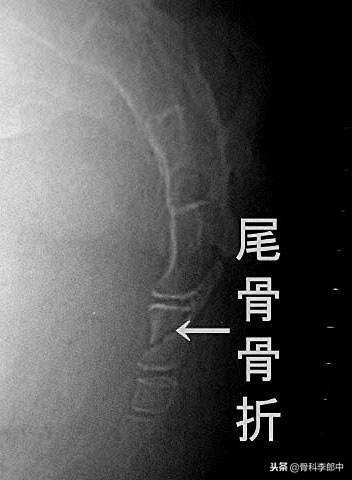

现在屁股后面非常疼痛,查体看看,疼痛的部位在臀沟尾骨的部位,大概明白了什么情况。建议拍个片子明确一下吧。拍个骶尾部正侧位片子。片子回来如下

尾骨是什么结构呢,既然叫尾骨,相当于动物的尾巴一样,只是人体尾巴已经退化,形成了尾椎骨。尾骨连接在骶骨的下面。如下图